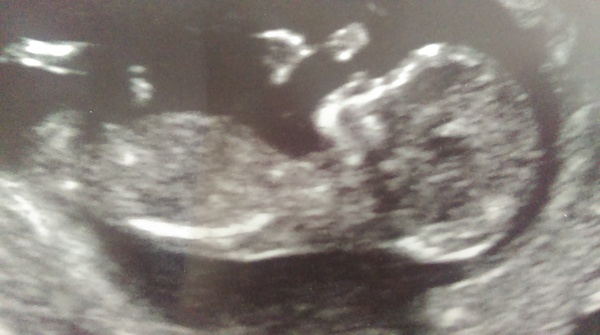

Had my scan today and I gained 2 days so now 12+2. Very wiggly baby. Lots of back flips. Ha ha.

BananaToast · 07/10/2014 16:40

Great scan pic kismac - love it's little nose! Glad you're feeling better.